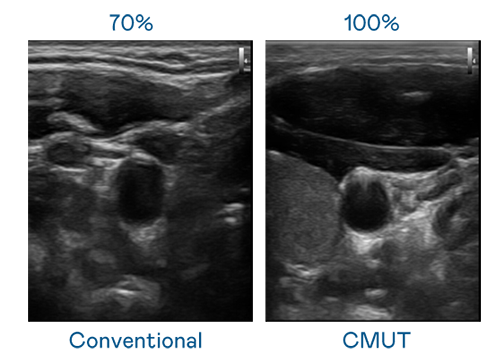

CMUT 技术是一种用电容式微机电元件来产生超音波讯号的技术。与传统 PZT 压电式技术相比,CMUT 频宽增加 30%,更宽频的超音波讯号让影像解析度大幅提升,是实现高影像品质医疗超音波扫描、促进精准医疗发展的关键技术。

超音波影像的解析度高低,首先取决于探头能发出的讯号频宽。龙8 CMUT 可提供高清晰的超音波讯号,提供高频宽、高灵敏度、影像纹理细节更高的超音波影像,协助医护人员缩短影像判读时间及利用精准的医疗影像进行诊断。